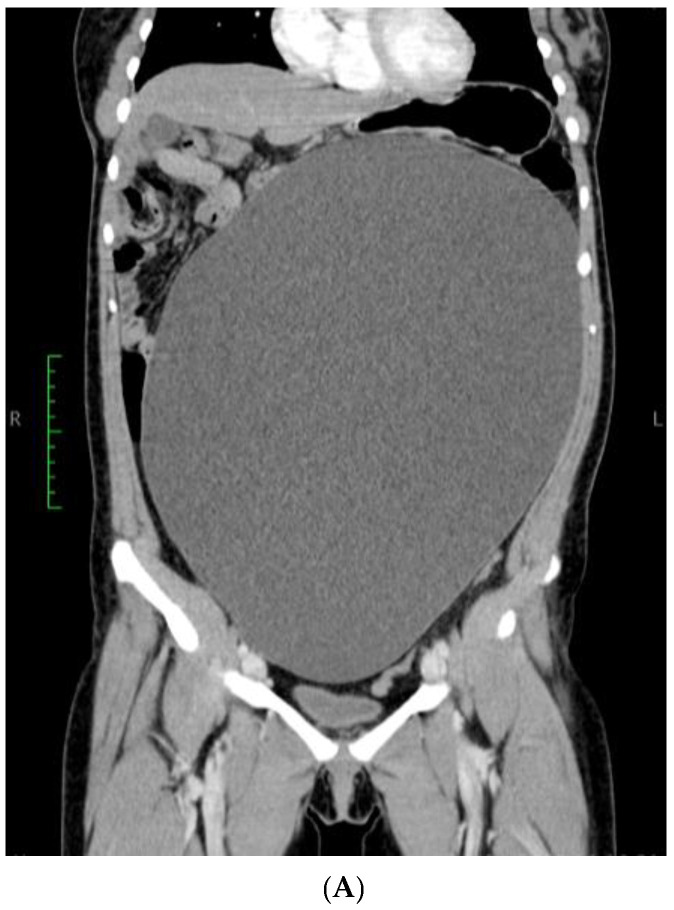

背景及临床意义:输卵管旁囊肿是一种特殊类型的附件囊肿,起源于位于输卵管和卵巢之间的阔韧带间皮,约占附件肿块的10%。有趣的是,大多数输卵管旁囊肿病例最初被误认为卵巢囊肿,每15名患者中只有1名在手术前被怀疑。病例介绍:我们报告了一例21岁女性的巨大输卵管旁囊肿,并附有一些代表性图像和文献综述。囊肿的治疗方法是手术切除附件,最终的术后组织病理学诊断为良性输卵管旁囊肿。结论:本病例强调需要包括输卵管旁囊肿在鉴别诊断盆腔肿块,特别是育龄妇女。据我们所知,这是迄今为止文献报道的最大的输卵管旁囊肿,基于总体尺寸和最高记录的抽吸液量,通过腹腔镜成功处理。本病例另一个值得注意的方面是巨大的输卵管旁囊肿与卵巢粘液囊腺瘤共存。

Background and Clinical Significance: A paratubal cyst, which makes up about 10% of all adnexal masses, is a specific type of adnexal cyst that develops from the mesothelium in the broad ligament located between the fallopian tube and the ovary. Interestingly, the majority of paratubal cyst cases are initially misidentified as ovarian cysts, with suspicion arising in only 1 out of every 15 patients before undergoing surgery. Case Presentation: We report a case of a giant paratubal cyst mimicking an ovarian cyst in a 21-year-old woman supported by some representative images along with a literature review. The cyst's therapeutic management was surgical removal of the adnexa and the final postoperative histopathological diagnosis was that of a benign paratubal cyst. Conclusions: This case highlights the need to include a paratubal cyst in the differential diagnosis of pelvic masses, especially in women of reproductive age. To the best of our knowledge, this represents the largest paratubal cyst reported in the literature to date, based on overall dimensions and the highest recorded volume of aspirated fluid, successfully managed via laparoscopy. A further notable aspect of this case is the coexistence of the giant paratubal cyst with an ovarian mucinous cystadenoma.